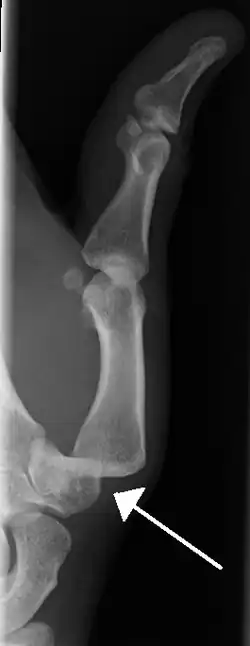

- Dislocation of the left index finger

- Radiograph of left index finger dislocation